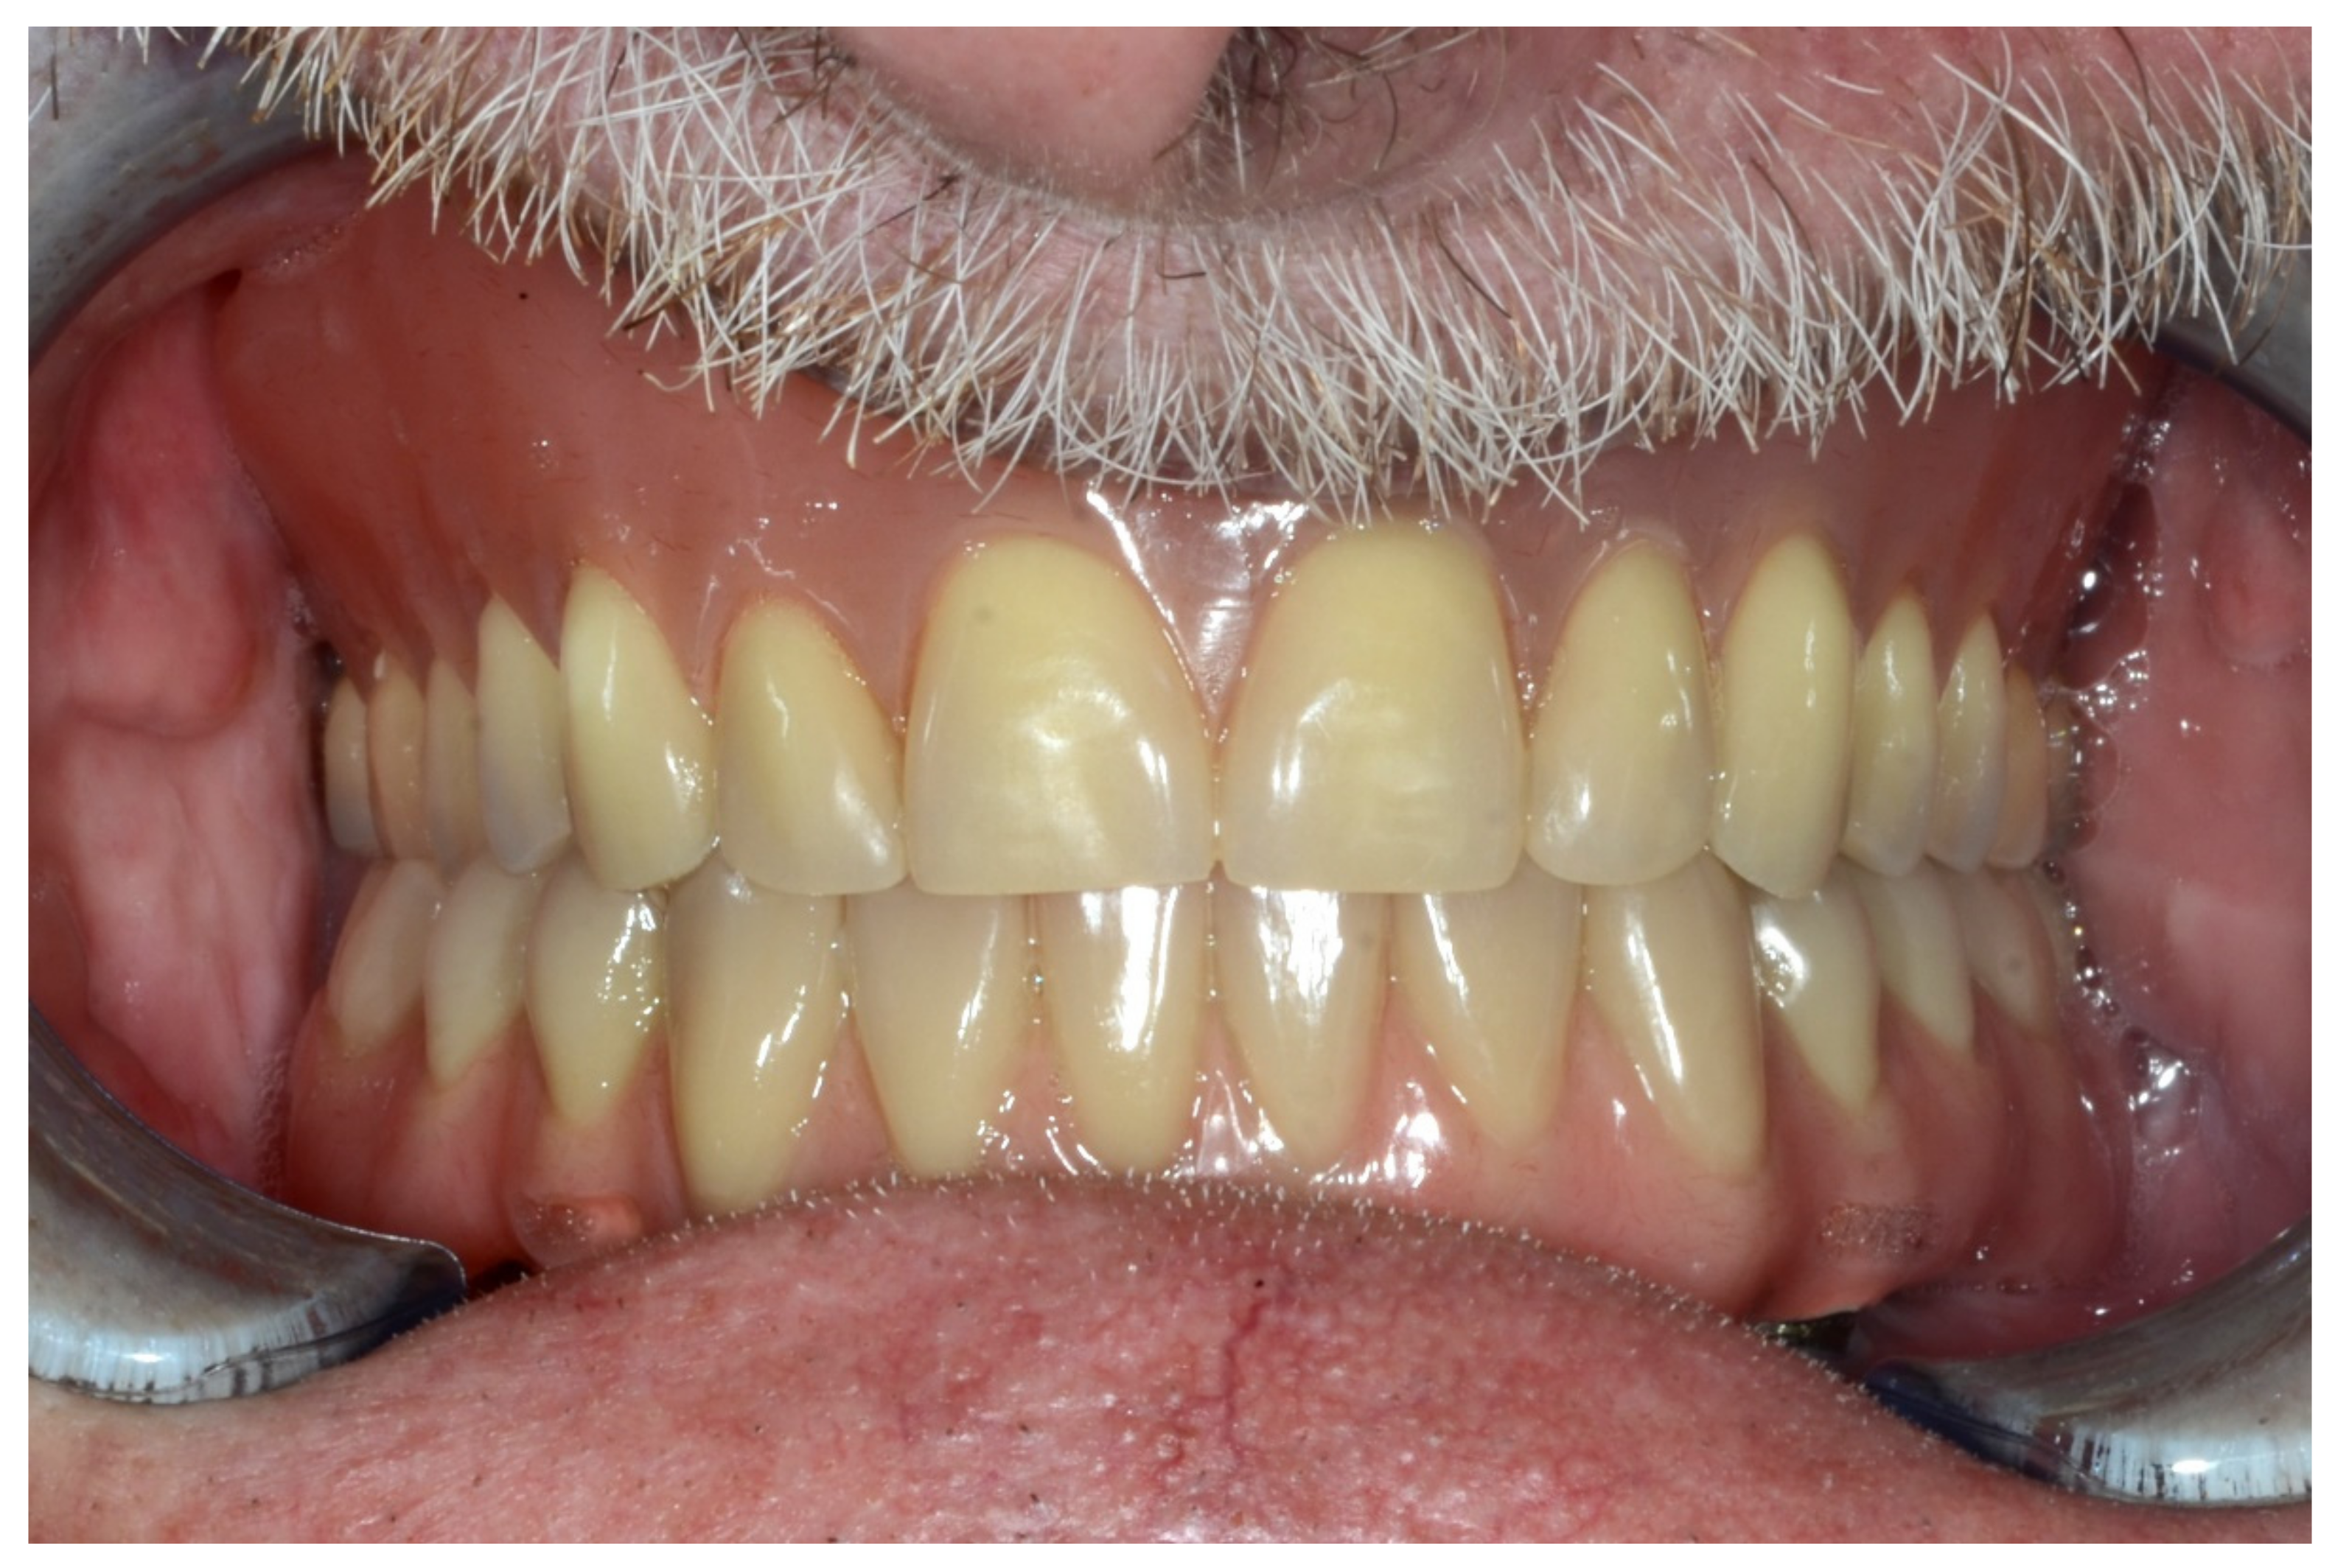

6.1.5. Postoperative (5-Years Follow-Up) Documentation:

A screw-retained provisional fixed prosthesis was used for 4 months to condition peri-implant mucosa, and in January 2019, the final prosthesis was installed. The occlusion was adjusted, and the patient received instruction for oral hygiene. A follow-up assessment at 5 years showed a stable cosmetic, biological and functional reconstruction (Figure 12, Figure 13 and Figure 14).

Figure 12.

Resting frontal close-up views.